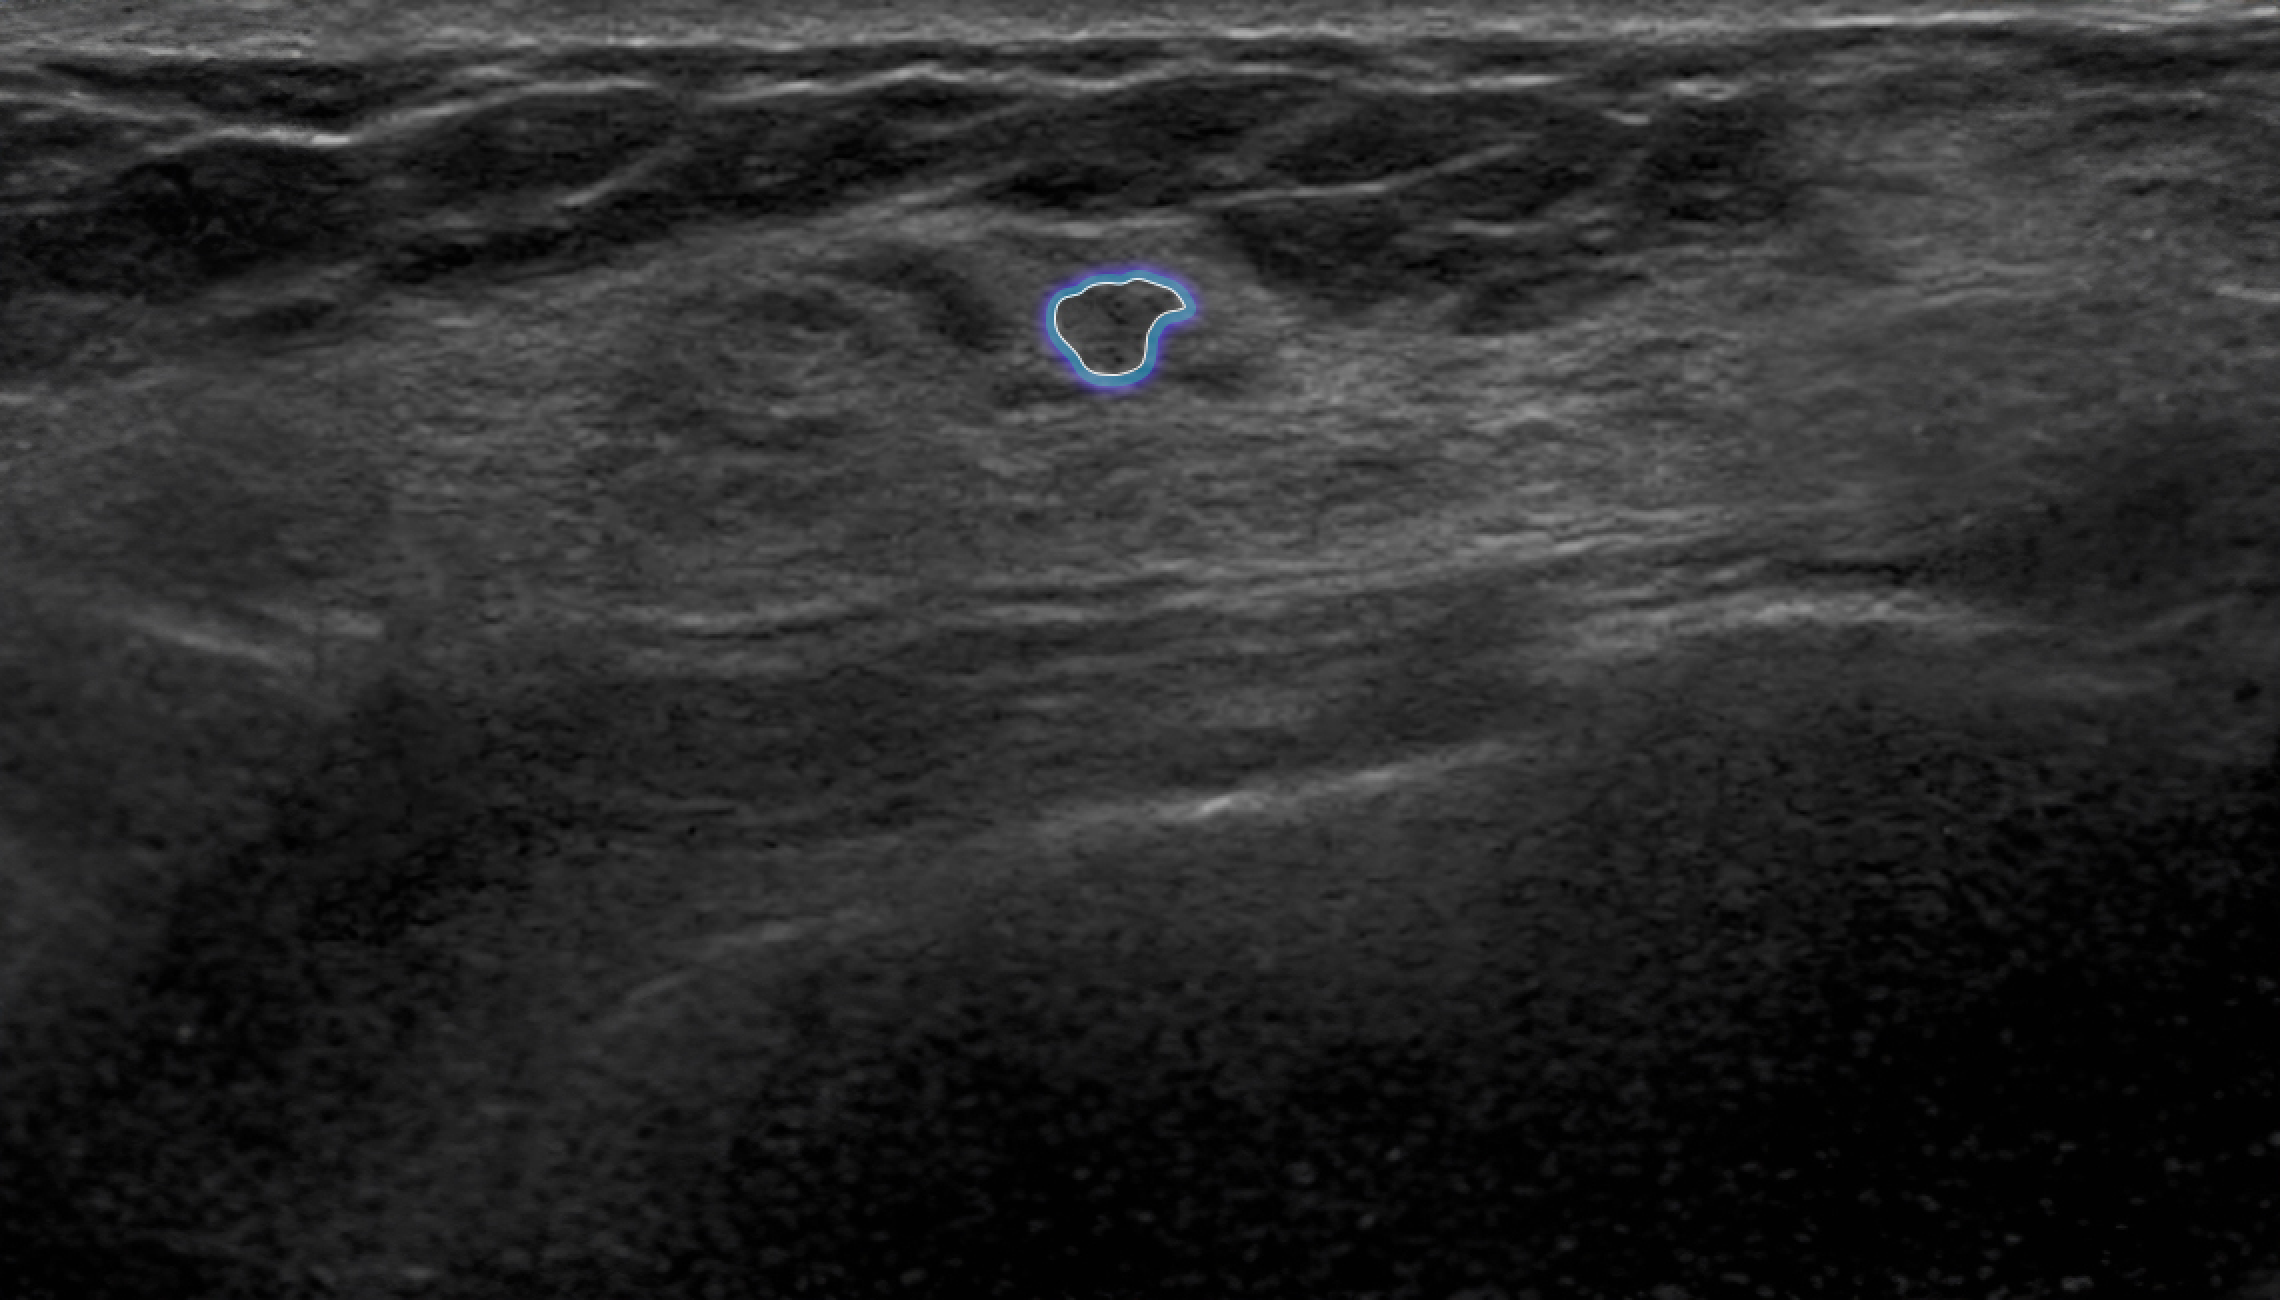

Automatic Detection of Abnormal Lesions

Automatically detects the locations of abnormal lesions in breast ultrasound images in real time.